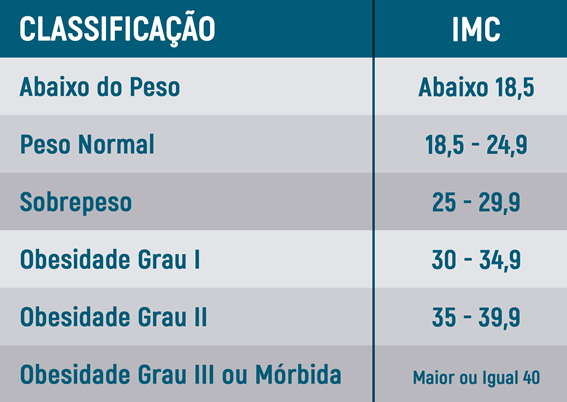

Calculando o IMC

Um indicador utilizado mundialmente para o controle do peso é o Índice de Massa Corpórea (IMC), que é calculado dividindo-se o peso pela altura ao quadrado.

O Balão Intragástrico está indicado para pessoas com IMC acima de 27 kg/m2, embora sua melhor indicação seja nas pessoas com obesidade leve (Grau I).